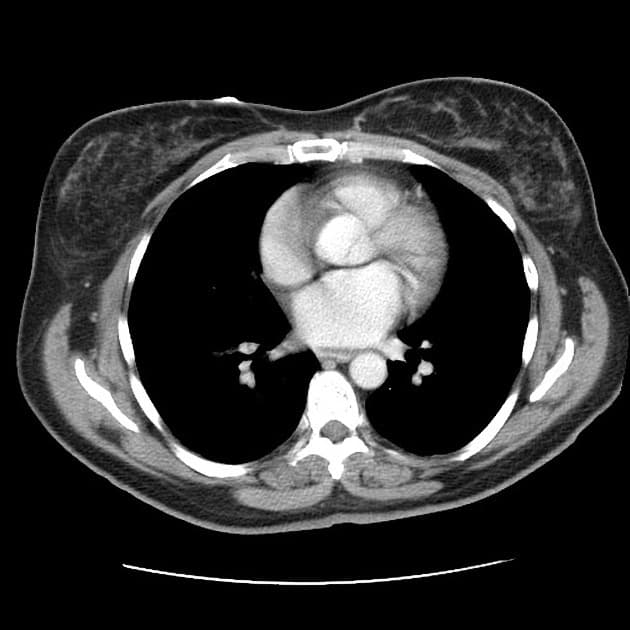

- Tràn dịch màng phổi (pleural effusion) hai bên mức độ nhẹ kèm theo xẹp phổi (atelectasis) vùng đáy.